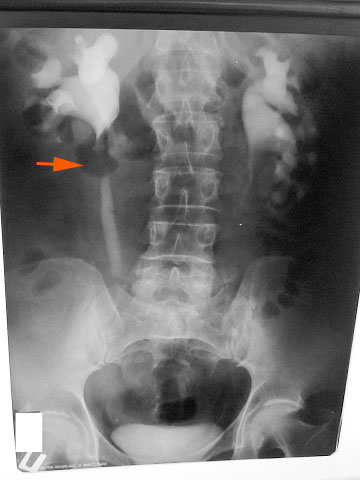

По УЗИ получается что эта штука должна быть примерно здесь - указано стрелкой - или чуть ниже.

Еще желательно проинспектировать нижнюю треть правого мочеточника при наполненном мочевом пузыре - непонятна атония мочеточника на всем протяжении, нужно искать причину.

В тот-же день, когда выложила снимки, пересмотрела эту женщину. Четко получилось вывести и проследить мочеточник в верхней и средней трети, нижнюю треть не увидела. Четко была видна внутримышечная локализация образования.